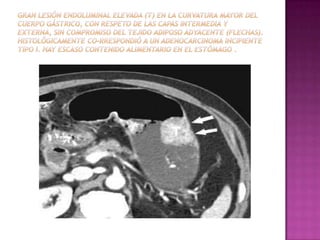

 Un tumor 1RIO tipo II b /CA gatrico

precoz, no se detecta MPR ni gastroscopia

virtual, solo Con CX.